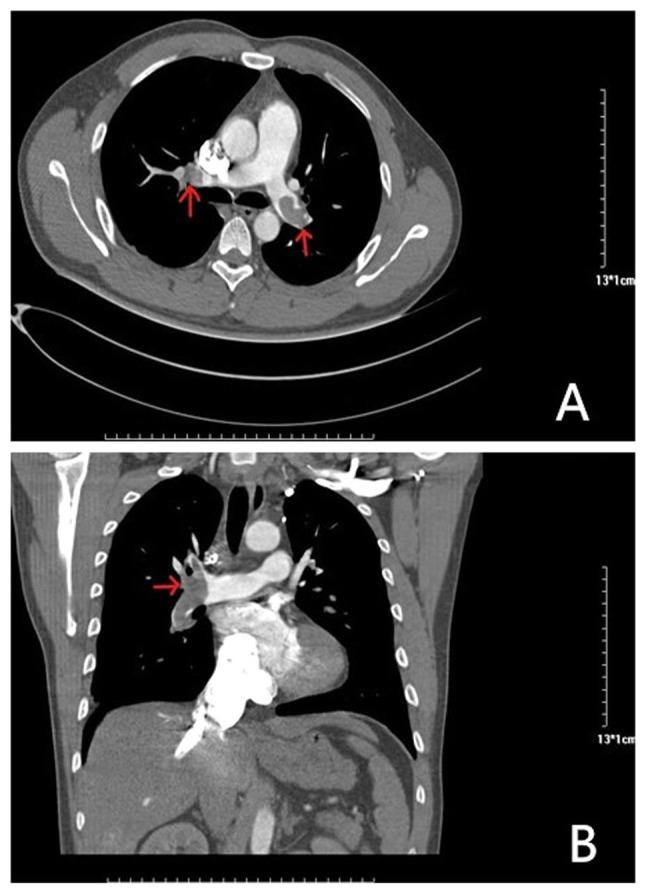

急性肺栓塞(PE)在老年患者中发病率较高,临床表现复杂,抗凝治疗策略也较为棘手。目前,对于老年PE患者抗凝治疗的选择标准了解有限。事实上,常用的抗凝药物维生素K拮抗剂华法林存在诸多缺点,包括治疗窗窄、药代动力学不可预测、食物和药物相互作用多以及基因多态性导致治疗反应不佳;因此,需要进行常规实验室监测。大多数老年PE患者无法坚持治疗方案,甚至中断治疗,临床医生在老年PE患者中启动口服抗凝药时也同样犹豫不决。这导致了抗凝治疗使用方面的困境以及患者预后较差。利伐沙班是一种直接Xa因子抑制剂,已显示出相当大的实际和临床优势,具有快速起效的药代动力学和药效学特征,抗凝效果可预测性增强,药物相互作用较少。基于随机对照试验和真实世界临床实践,利伐沙班也被认为是一种安全有效的抗凝药物,这些优势提高了老年PE患者的治疗依从性。因此,本综述聚焦于利伐沙班治疗老年PE患者的现状,并阐述其在改变患者当前抗凝治疗方案方面的意义。预计利伐沙班将成为老年PE患者治疗的良好选择。